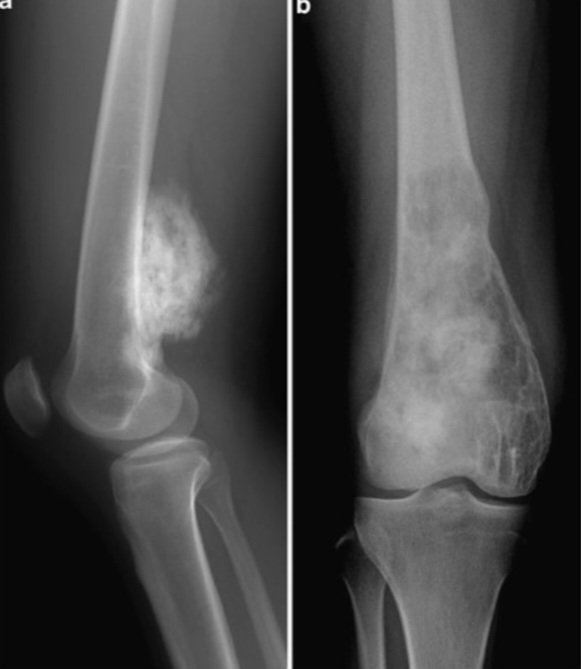

1- الأشعة السينية X-Ray:

- تستخدم للفحوصات الروتينية.

- سريعة وغير مكلفه ماديا.

- الأكثر شيوعًا ومتاح على نطاق واسع.

- تأخذ صورة ثنائية الأبعاد(2D).

- تستخدم في الإصابات لكشف الكسور.

- تستخدم ايضا لكشف الالتهاب الرئوي في الصدر وبعض الاورام السرطانية.

- نسبة الإشعاع بسيطة.